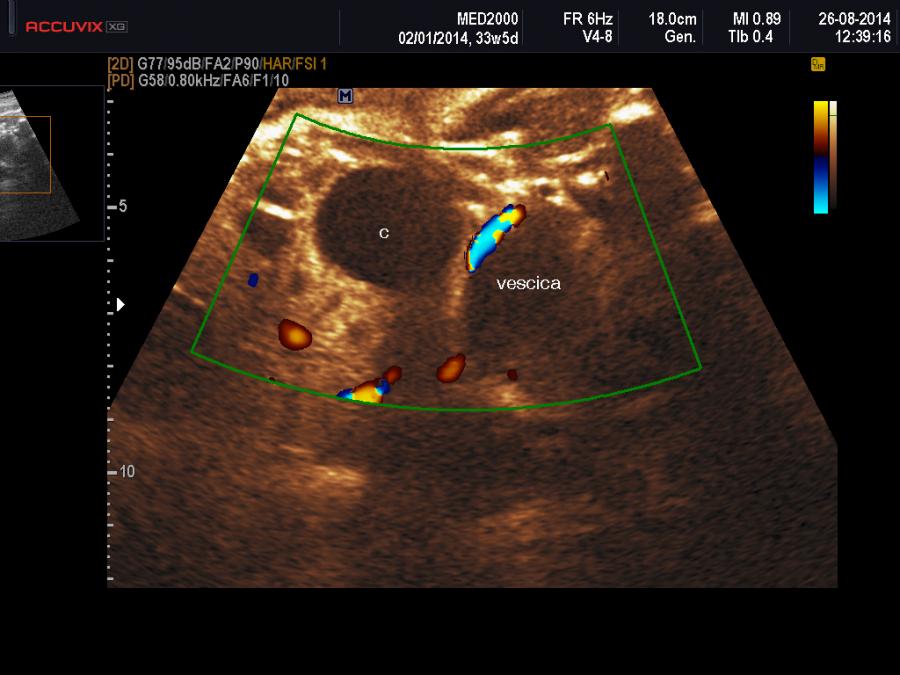

Una cisti ovarica fetale si manifesta comunemente come una Cisti Uniloculare a parete sottile localizzata superiormente e parasagittalmente alla vescica; occasionalmente può essere visualizzata al suo interno una cisti figlia aspetto questo patognomonico di cisti ovarica. L'aspetto può essere anche quello di una cisti complessa e in caso di emorragie endocistiche o di torsione possono assumere l'aspetto di Cisti Uniloculari Solide; in tali casi possono presentarsi con dei setti, con dei livelli o con echi interni mobili (Trinh TW  et al. 2015). Meno frequente è la presenza di cisti bilaterali.

Importanti per la diagnosi sono due elementi: 1) sesso femminile, 2) differenziazione dalla vescica urinaria: tale distinzione è agevole considerando che è possibile evidenziare, con l'ausilio del color-doppler, le due arterie ombelicali che decorrono lateralmente alla vescica.